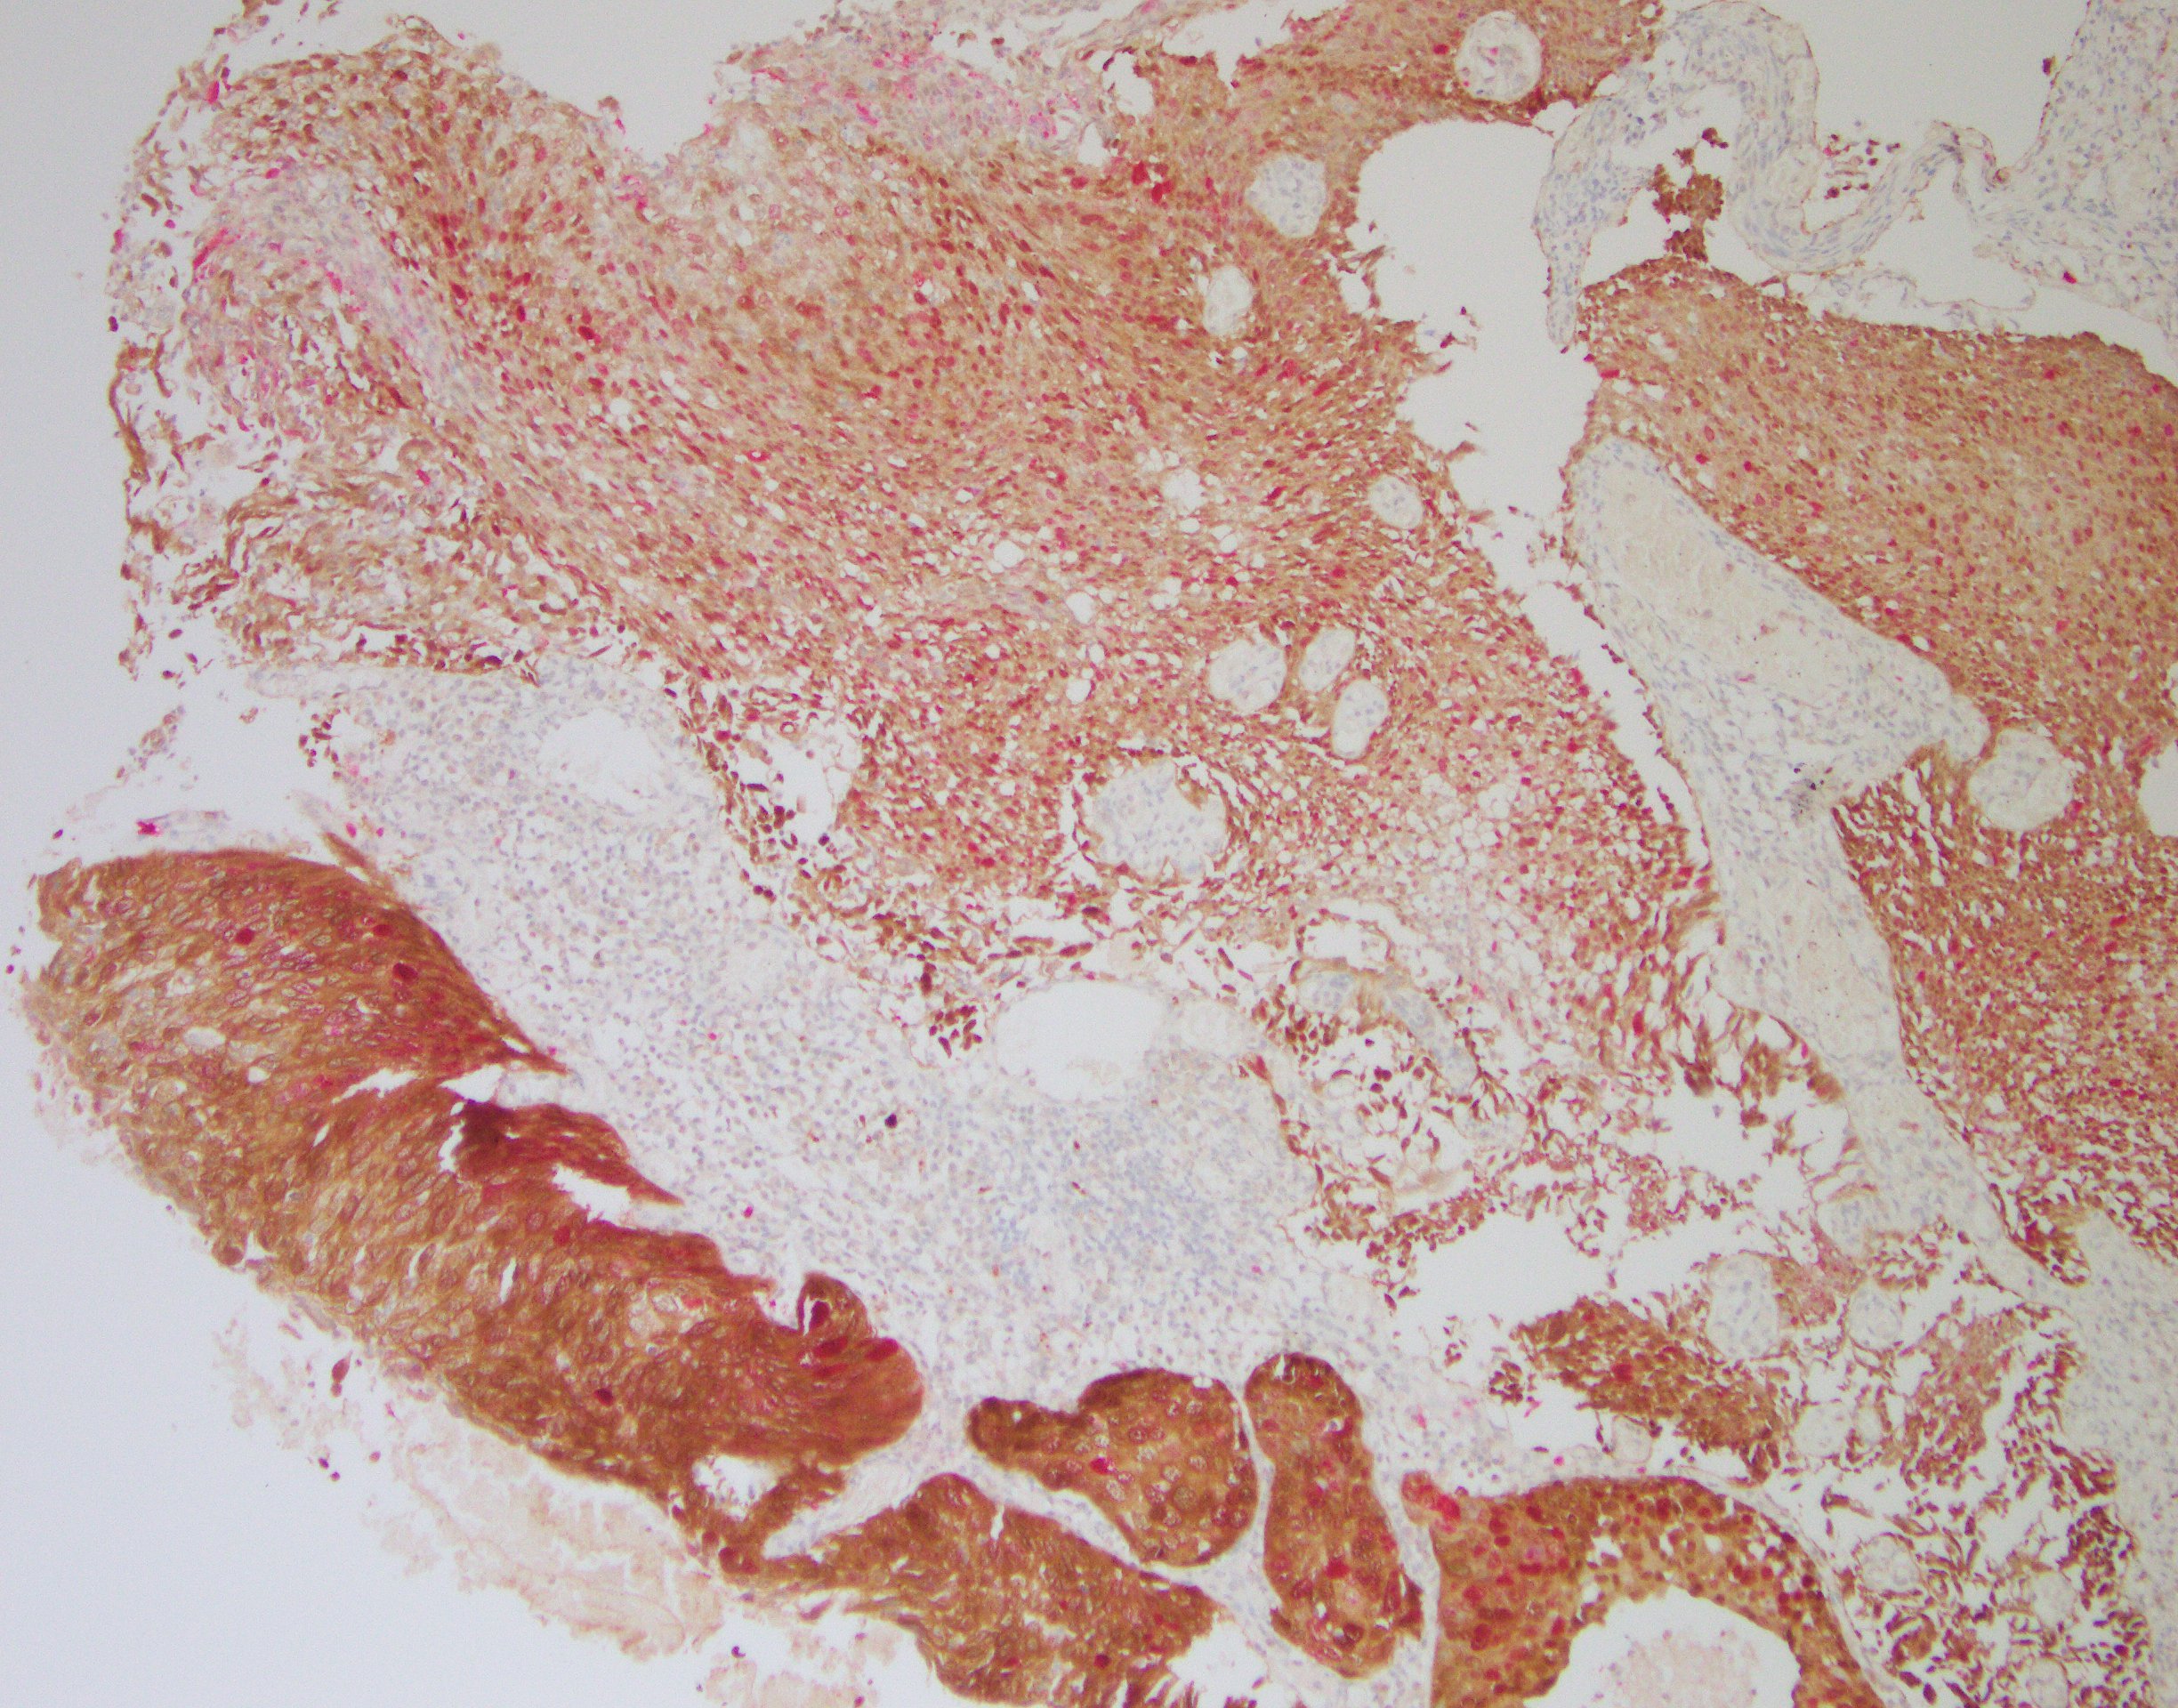

【新品】p16/Ki-67檢測試劑盒(免疫組織化學法)

本試劑基于免疫組織化學檢測原理:組織經抗原熱修復處理后與一抗試劑(p16/Ki-67)進行孵育,在原位形成目標抗原-抗體復合物;抗原-抗體復合物中的 p16 抗體與辣根過氧化物酶(HRP)標記的聚合物二抗孵育結合,通過催化二氨基聯苯胺(DAB)在細胞漿/細胞核上形成棕色沉積物;抗原-抗體復合物中的 Ki-67 抗體與堿性磷酸酶(AP)標記的聚合物二抗孵育結合,通過催化 AP 顯色液在細胞核上形成玫瑰紅色沉積物。光學顯微鏡下通過觀察細胞的染色情況來確定是否存在目標抗原的表達。

高級別CIN組織,p16/Ki-67雙染